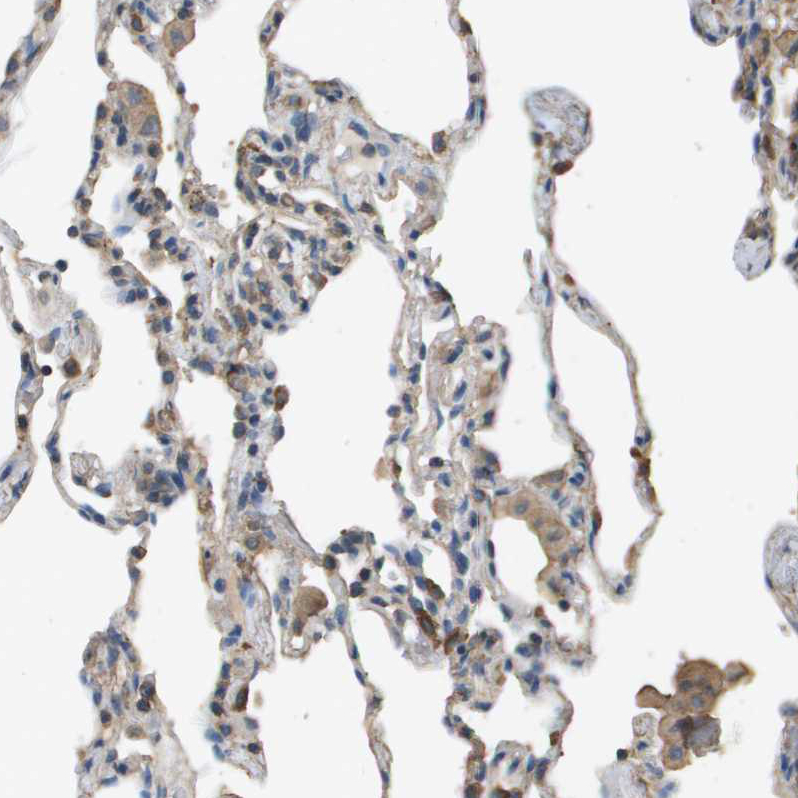

Immunohistochemical staining of human lung shows weak cytoplasmic positivity in macrophages.